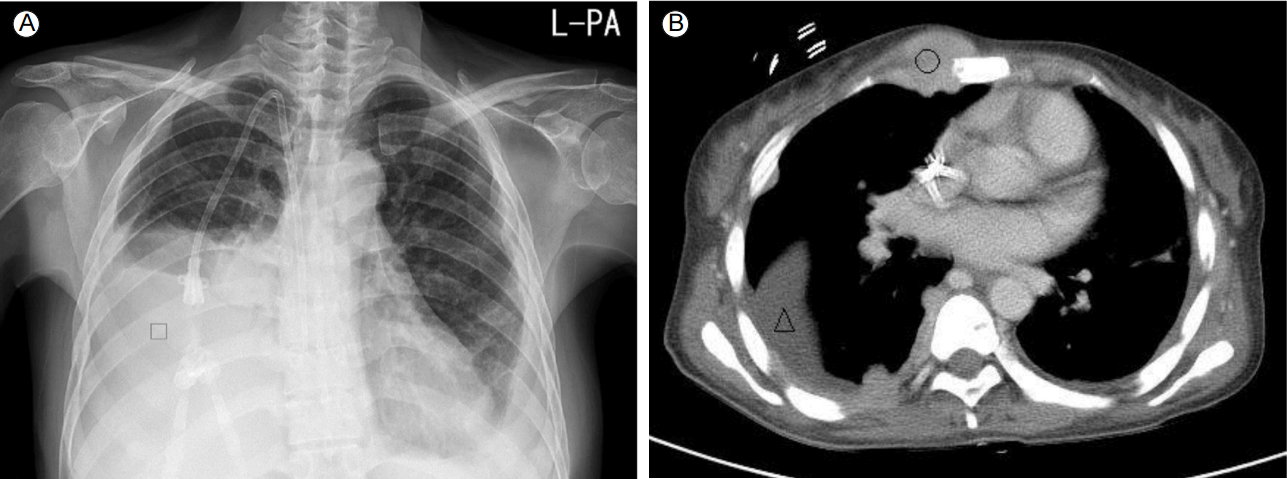

방사선학적 소견: 2015년 8월 17일 시행한 흉부 X선 촬영에서 다량의 우측 흉수 소견을 보였다(Fig. 2A). 2015년 8월 24일 시행한 흉부 전산화단층촬영에서 6월 2일 영상 소견에 비해 대부분의 흉벽내 체외뼈 형질세포종이 감소 소견을 보였으나 우측 흉수와 함께 우측 전 흉벽 부위로 체외뼈 형질세포종이 새로 발생하였다(Fig. 2B).

Figure 2.

Chest X-ray and chest computed tomography (CT) scan. (A) Right pleural effusion of large volume was detected (□). (B) Extraosseous plasmacytomas in the right anterior chest wall was increased in size (○), and the right pleural effusion was of lesser volume (△) than that noted in the CT scan 2 months previously.